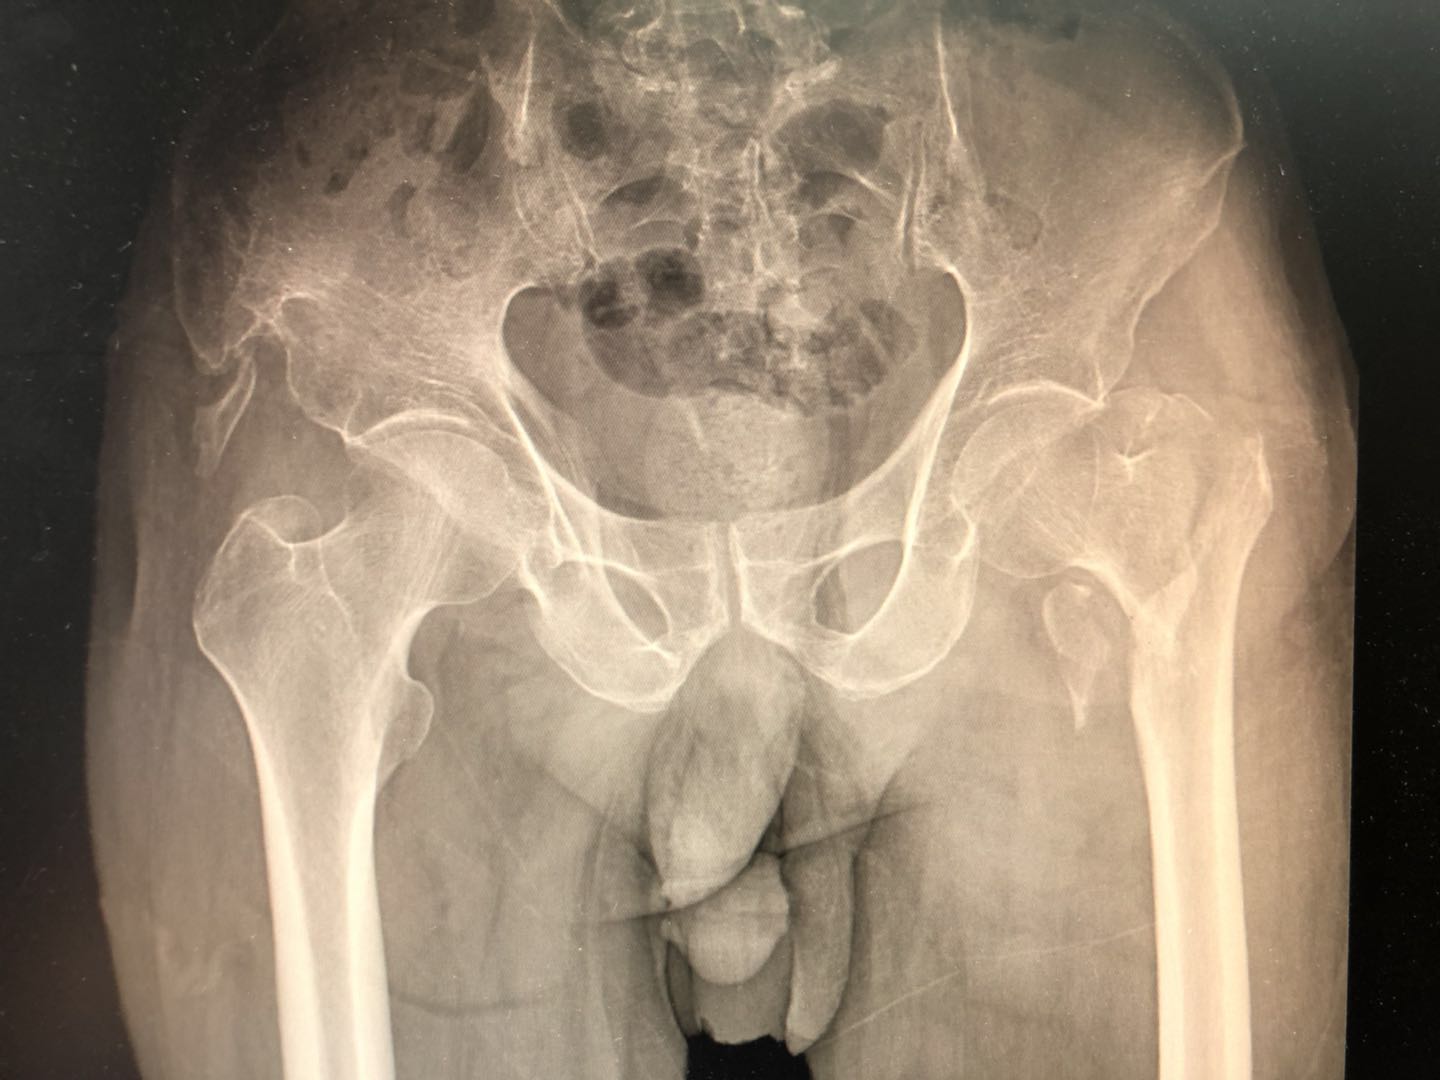

78岁的老年男性,平时身体健康,因为腰痛在A医院诊断为腰椎间盘突出,行保守治疗期间不慎摔倒,因为老人家伴有明显的骨质疏松,摔倒后出现左髋关节疼痛,活动受限,没办法下地走路,在A医院拍了一个片子如下图所示:

X光提示一个左侧股骨粗隆间骨折,这跟小黑锅平时讲的股骨颈骨折是两个东西,但对于老百姓来讲都是腿的骨头断了,就暂时这么理解吧!对于这种骨折来说,可以说是老人家的“最后一次骨折”为什么这么说呢?